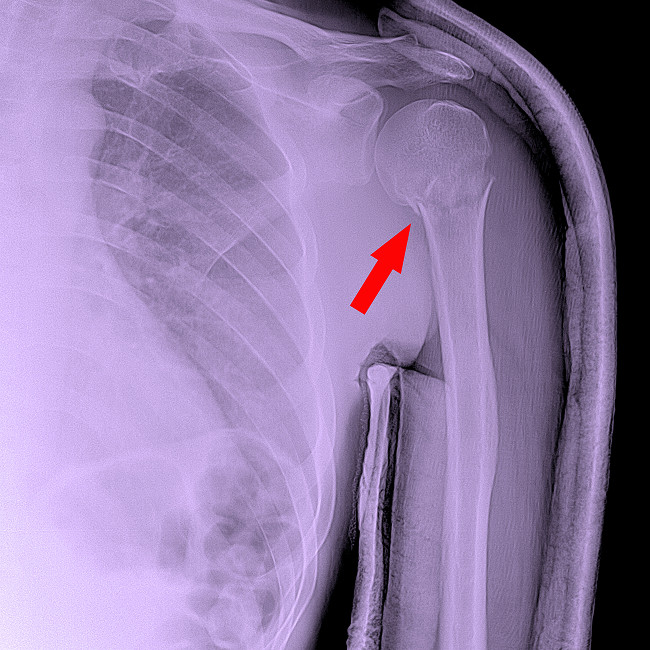

Proximal Fractures

Proximal fractures occur in the upper part of the humerus—in the area of ​​the head, anatomical neck, and surgical neck. They most often occur in older adults after falling on an outstretched arm. These injuries often involve displacement of the fragments, requiring precise fixation. In some cases, a doctor applies a plaster cast to a humeral fracture, but if the fracture is significantly displaced, surgical osteosynthesis using a plate or screws is performed.

A humeral head injury is dangerous because it can affect the shoulder joint, causing subsequent limited motion, pain, and deformity.